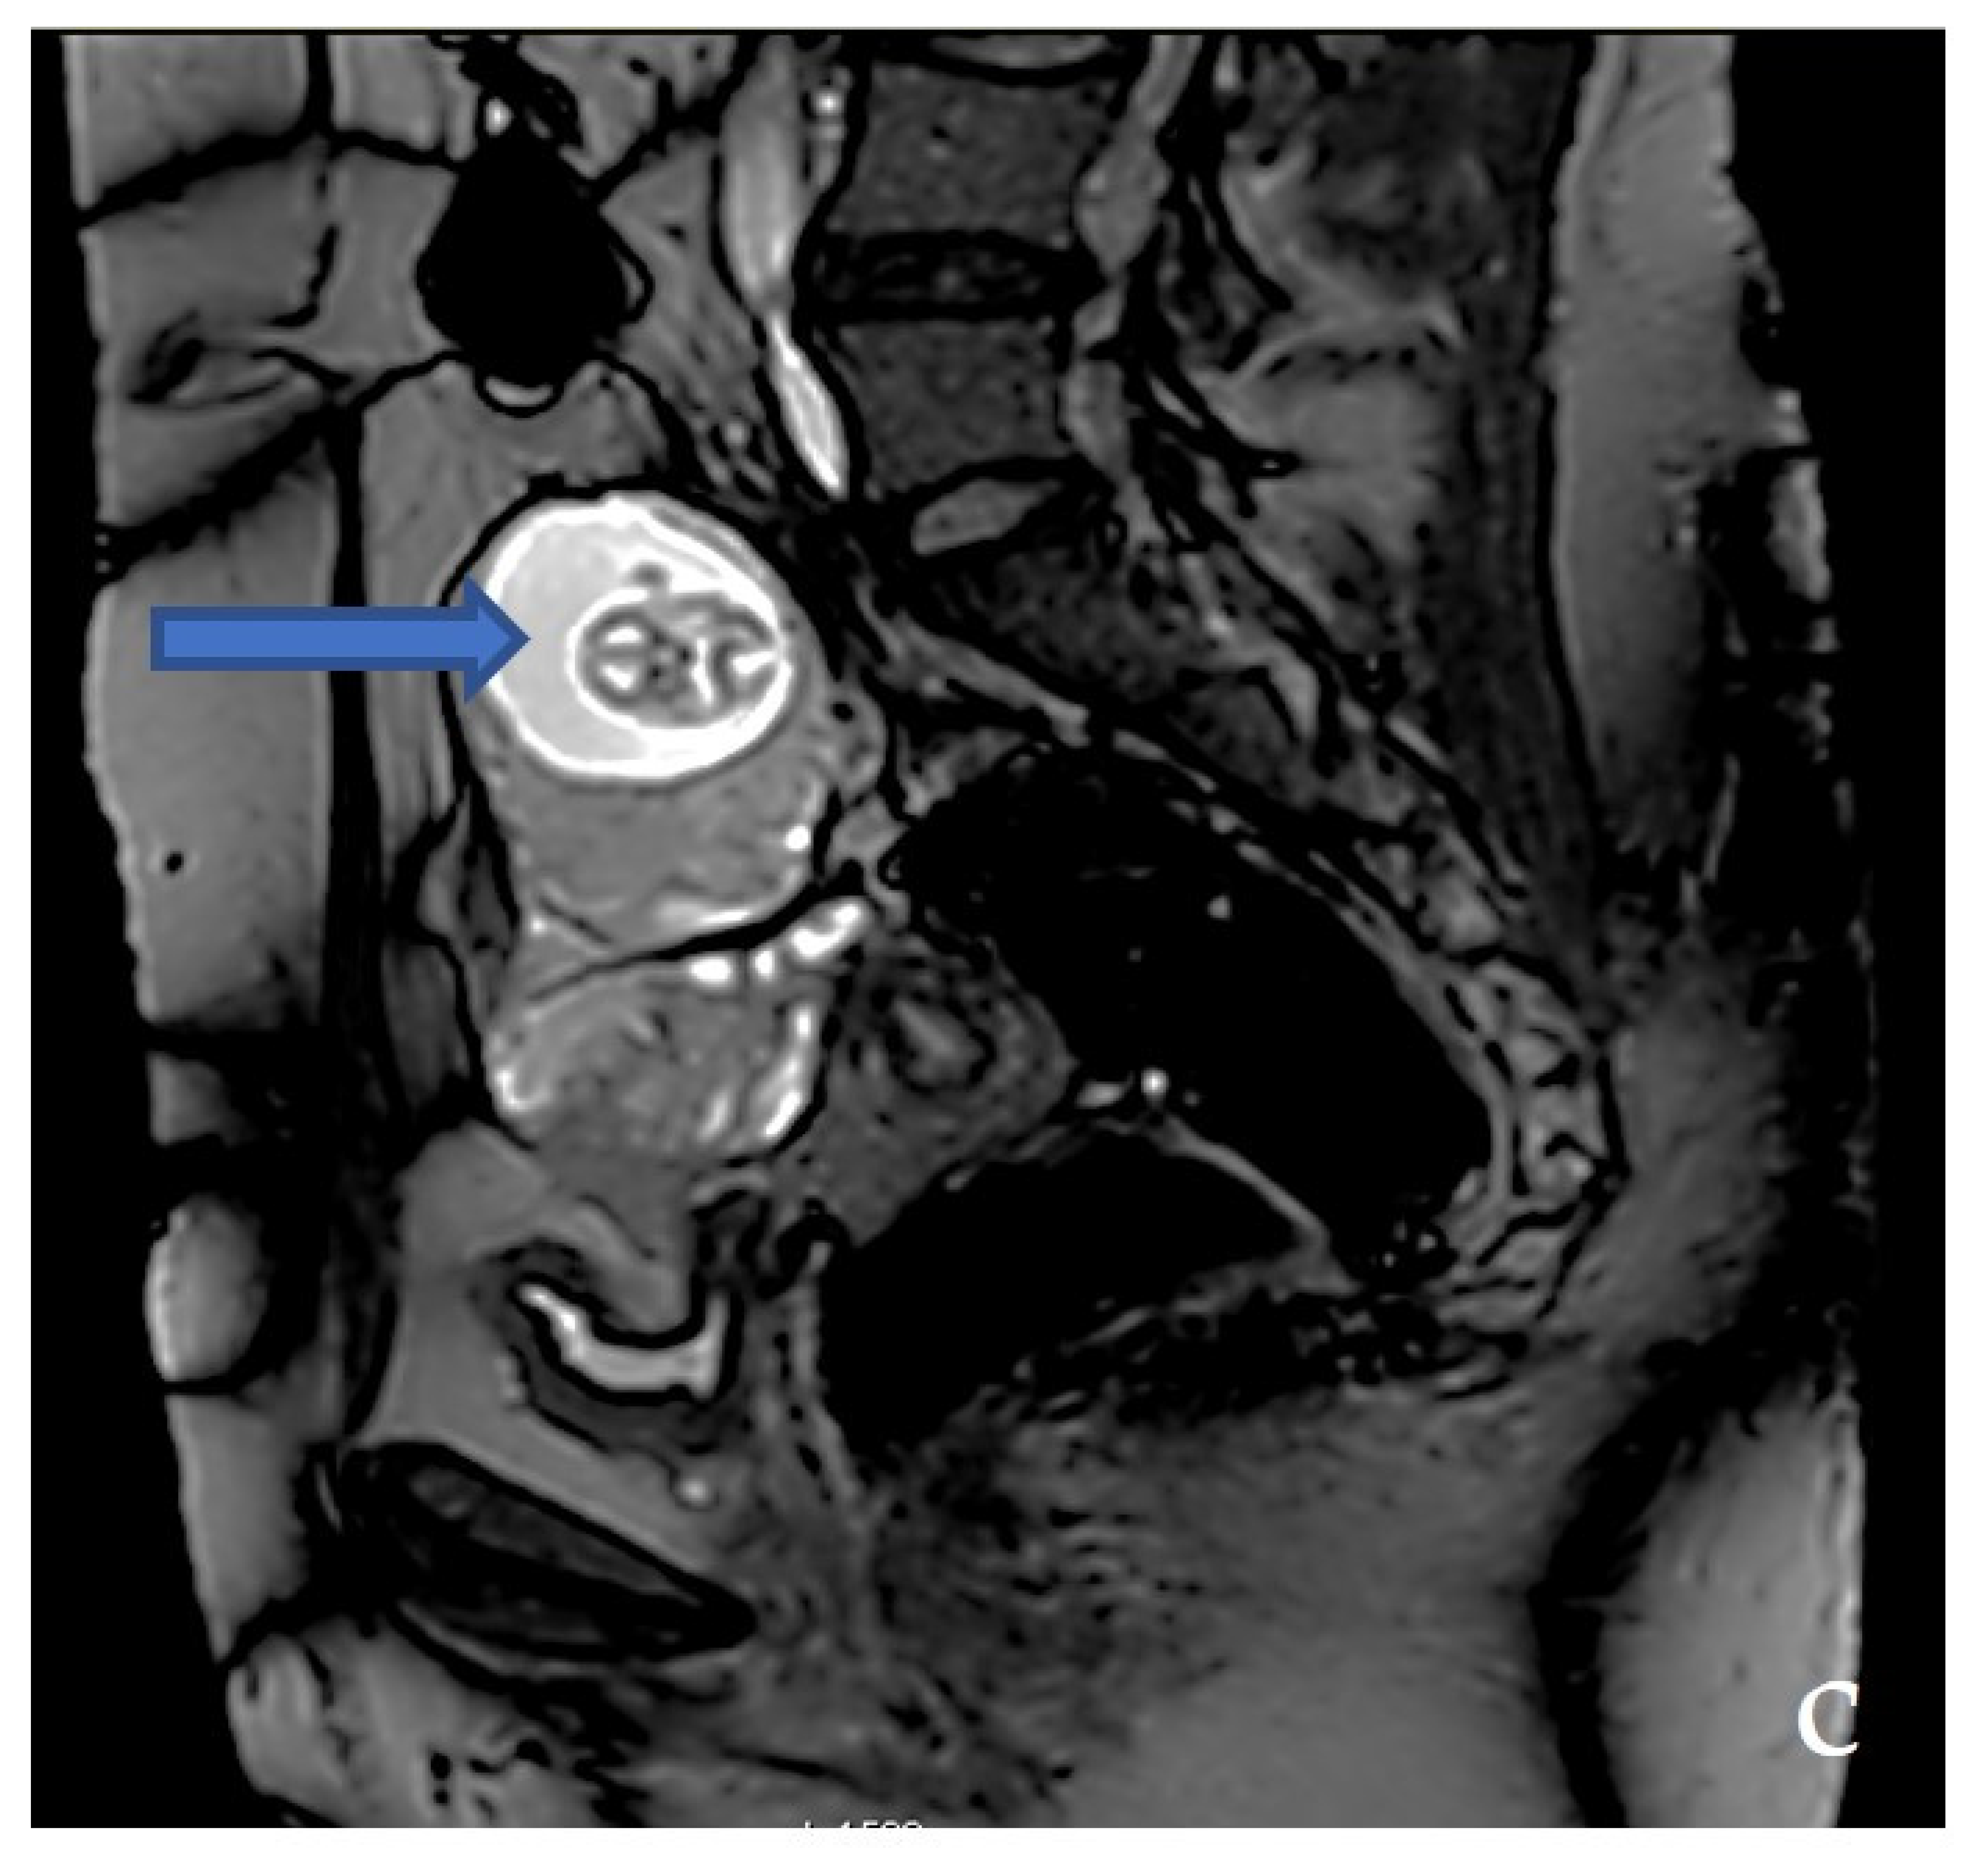

2.3. Diagnostic Assessment and Investigations